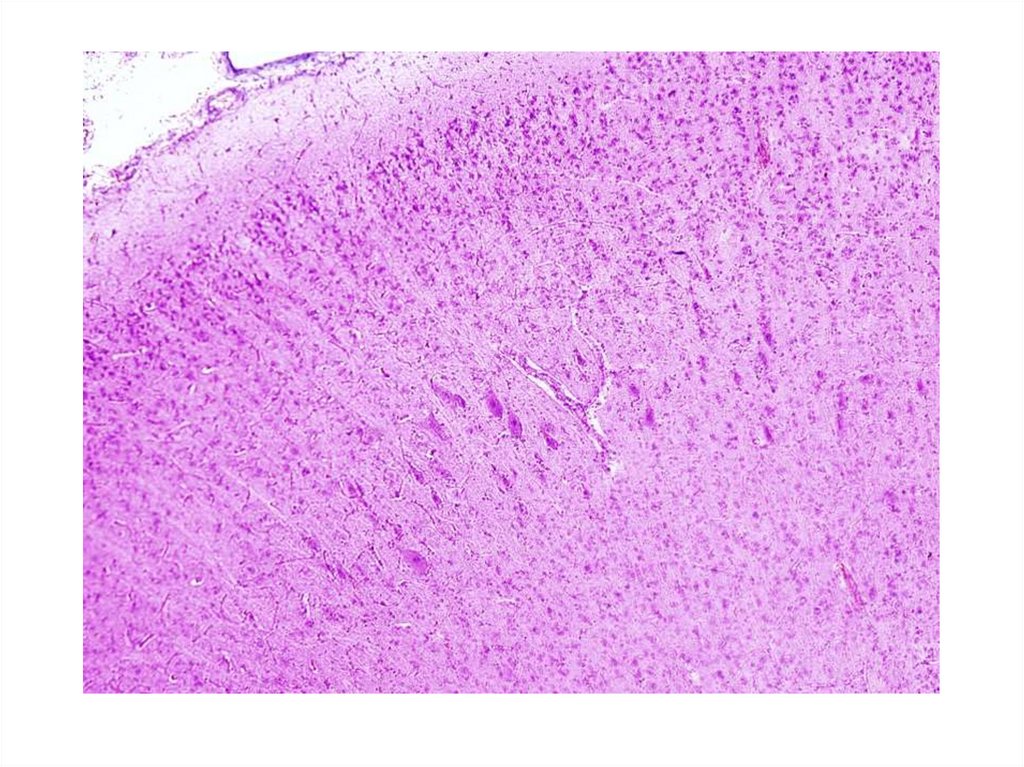

Частная гистология